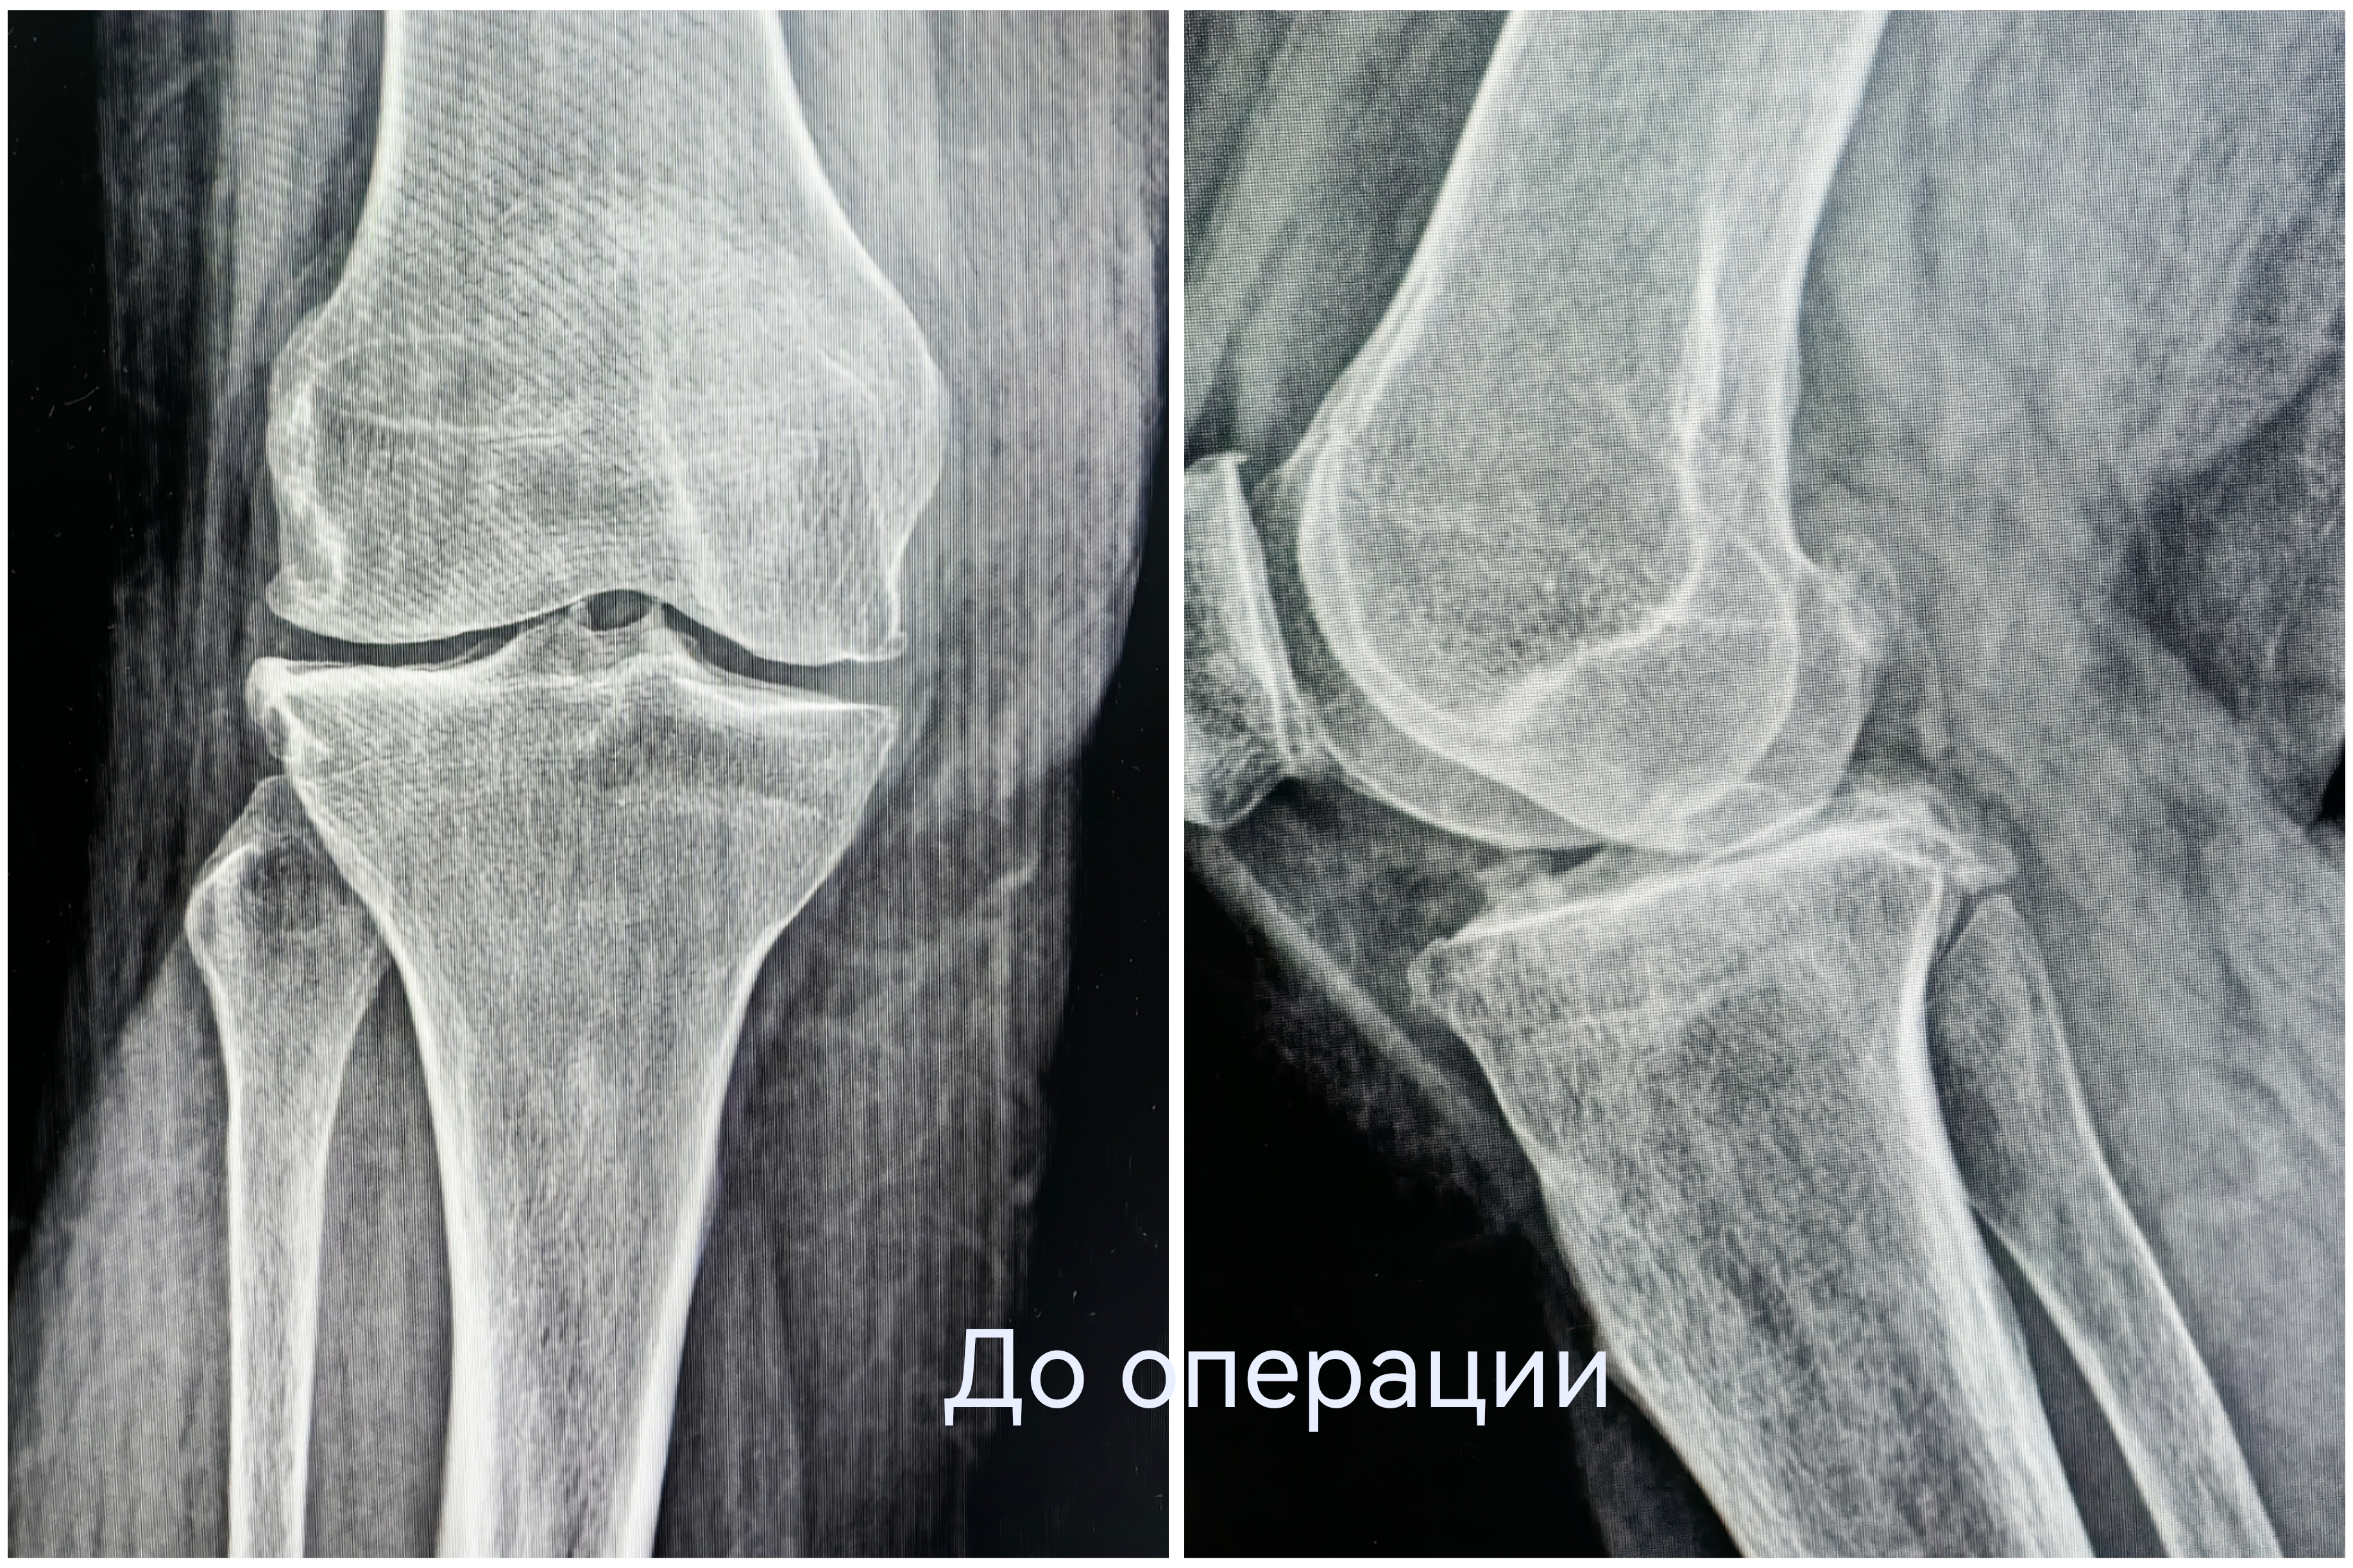

Чтобы избавиться от мучительной боли в колене, наша 55-летняя пациентка готова была избавиться от всего сустава. При госпитализации женщина настроилась на эндопротезирование. Однако травматологи-ортопеды выбрали другую тактику. При вальгусной деформации и деформирующем артрозе второй стадии коленный сустав оставался достаточно сохранным. Чтобы спасти его от замещения металлоконструкцией, была выполнена корригирующая остеотомия.

Суть операции – в исправлении нарушенной оси конечности. После перестроения и выравнивания костей голени нагрузка собственного веса смещается с пораженной части сустава на здоровую. Таким образом, болевой синдром регрессирует, а износ сустава замедляется.